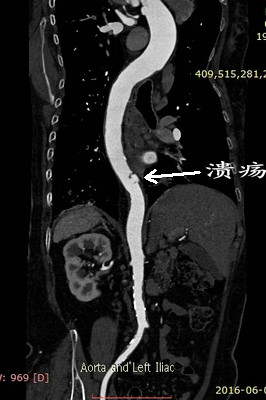

但术前的CTA评估又发现新的问题(图1、2),患者同时合并左侧锁骨下动脉的重度狭窄,狭窄>80%,平素血压多测量右上肢,并未发现,入院测量双上肢血压差别高达30mmHg!更困难的是,主动脉溃疡的破口位于胸10椎体部位,行覆膜支架腔内治疗,患者术后截瘫风险较大。患者病情危重,一旦主动脉破裂出血,死亡率极高!患者家属再次陷入恐慌,在此两难之际,王兵教授果断决策,手术要做,且决定同时介入治疗锁骨下动脉狭窄,因为锁骨下动脉狭窄的解除不仅能改善患者脑部及上肢供血,同时对脊髓供血起到良好的代偿作用,但即便如此,术前也与麻醉科胡强夫主任反复沟通,做好脑脊液穿刺引流准备,最大限度降低截瘫风险。

图1:左侧锁骨下动脉重度狭窄 图2:主动脉透壁性溃疡